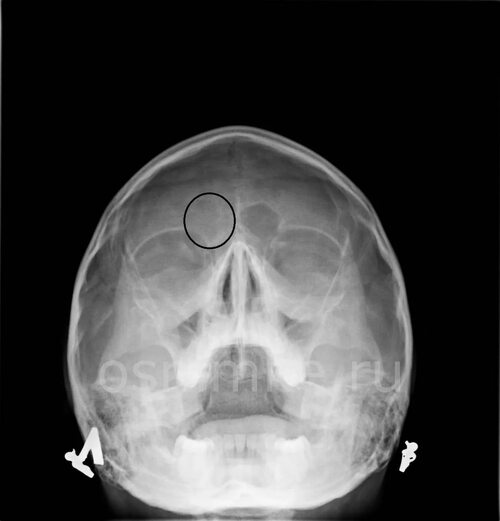

Фото 3: Диагностика фронтита

Третья фотография показывает процесс диагностики фронтита. Врач может использовать эндоскопическую камеру для осмотра полости носа и обнаружения воспаления.